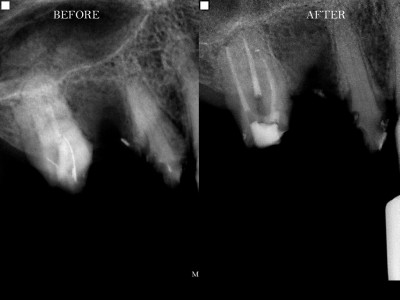

Περιστατικά